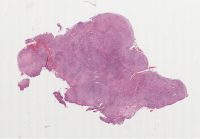

AANP2002-3.svs

8000 x 7549

@ 20X